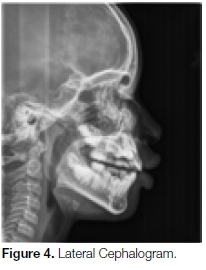

Examination of a lateral cephalogram (Figures 4 and 5) demonstrated, on the lingual aspect of the impacted tooth, a radio-dense bell-shaped structure with invagi-nations and a central radiopaque spherical mass. It was not clear whether it was attached to the tooth or not.

Lateral cephalograms are used to assess the dental, skeletal and soft tissue relations of an orthodontic patient. Lateral cephalometric analysis has been used widely in orthodontics as an investigative technique to evaluate growth and treatment responses.6 The cephalogram also helps in the identification of anomalies or pathologies present in the jaws as well as impacted teeth. However, there are several disadvantages.

Cephalometric analyses are based on the expectation of excellent superimposition of the left and right sides at the mid-sagittal plane. Such perfect superimpositions are rarely seen due to slight facial asymmetry in individuals as well as faulty head positioning. Major errors are also encountered due to the ambiguity in locating anatomical landmarks due to poorly defined outlines and shadows.12